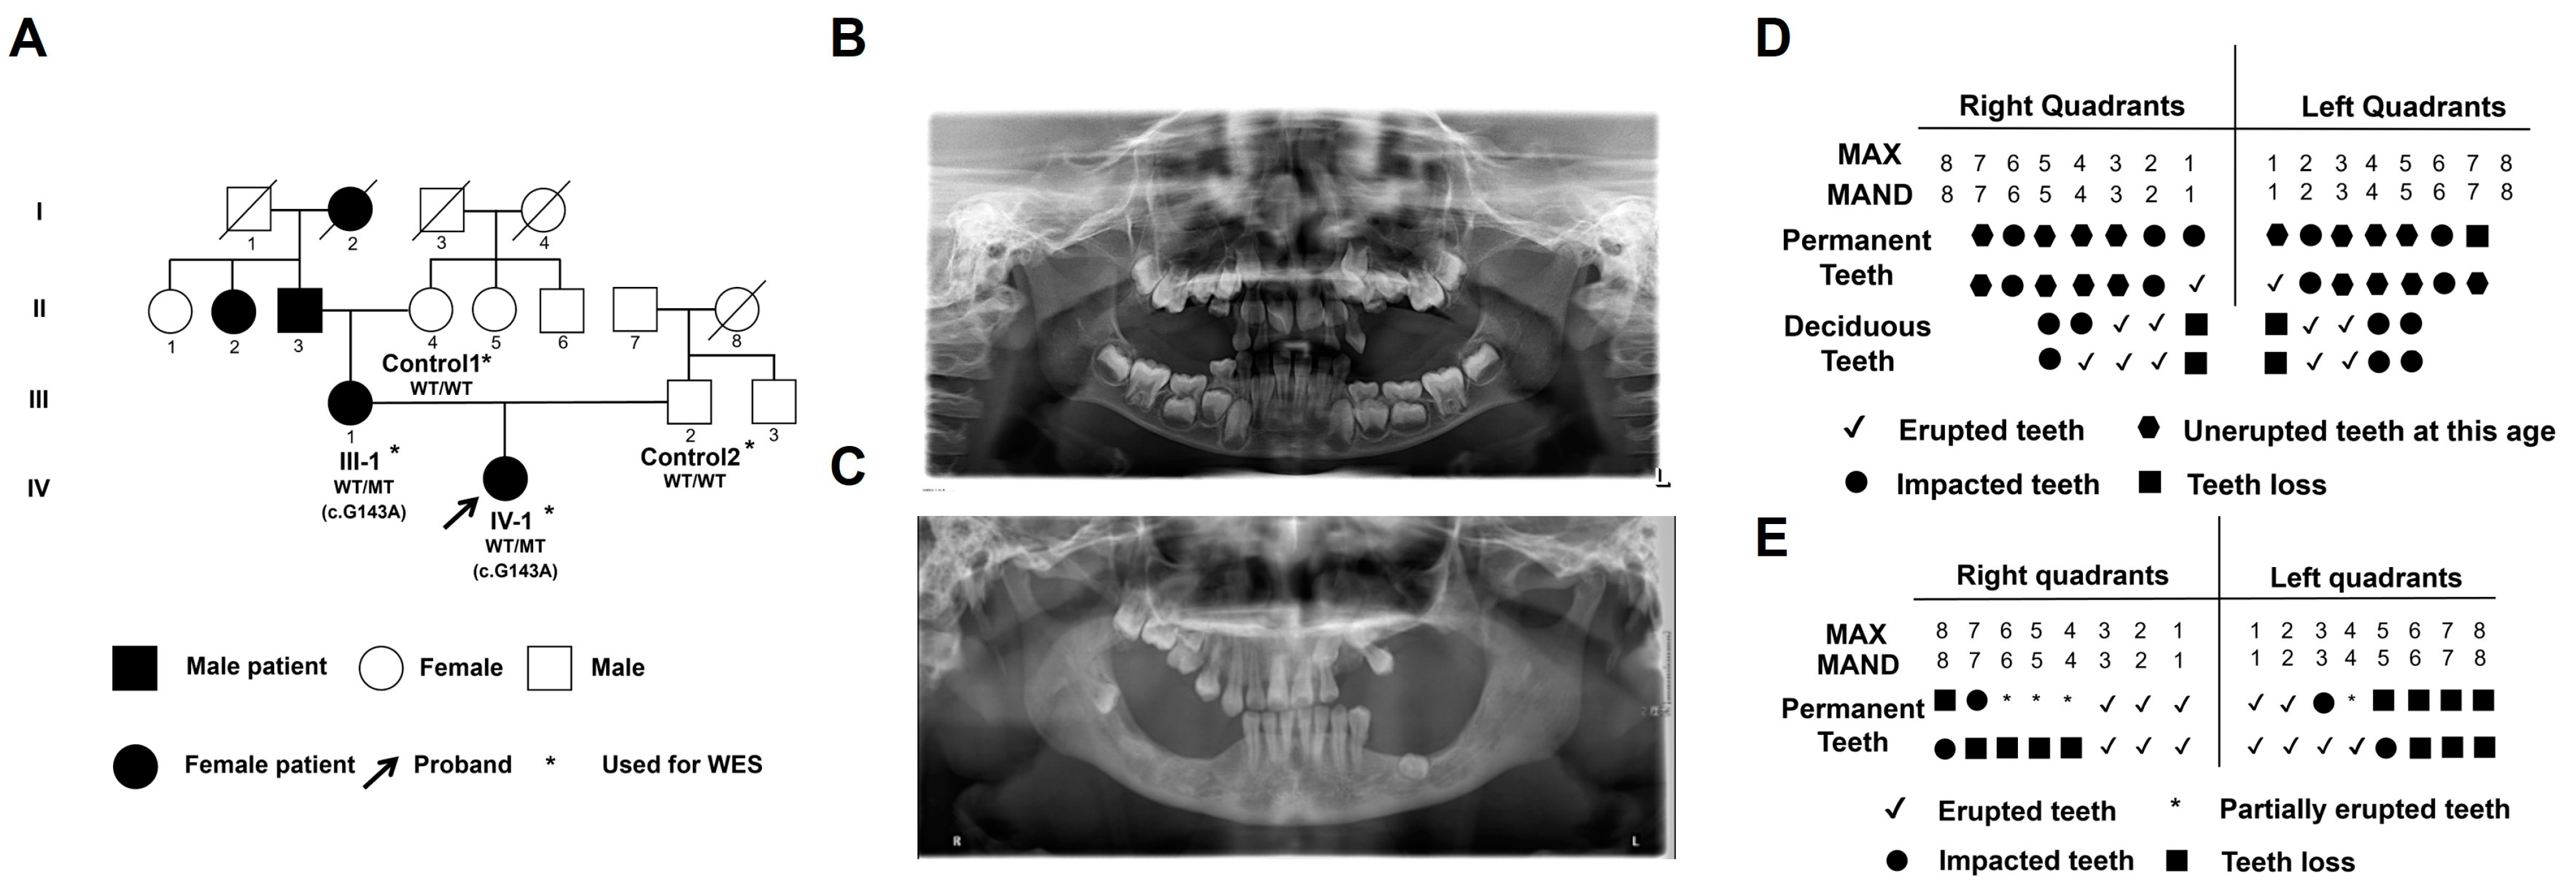

2.1. Clinical Characteristics of Primary Failure of Eruption (PFE) Individuals

| Patient | Sex (F/M) | Clinical Feature of PFE | Mutation | |||

|---|---|---|---|---|---|---|

| Nucleotide | Codon | Type | Location | |||

| I-2,II-2 | F | Doubtful | Unknown | Unknown | Unknown | Unknown |

| II-3 | M | Doubtful | Unknown | Unknown | Unknown | Unknown |

| III-1 | F | Yes | 143G > A | S48L | Missense | Extra-membrane |

| IV-1 | F | Yes | 143G > A | S48L | Missense | Extra-membrane |

| Control 1 | F | No | Wild-type | Normal | Normal | Extra-membrane |

| Control 2 | M | No | Wild-type | Normal | Normal | Extra-membrane |